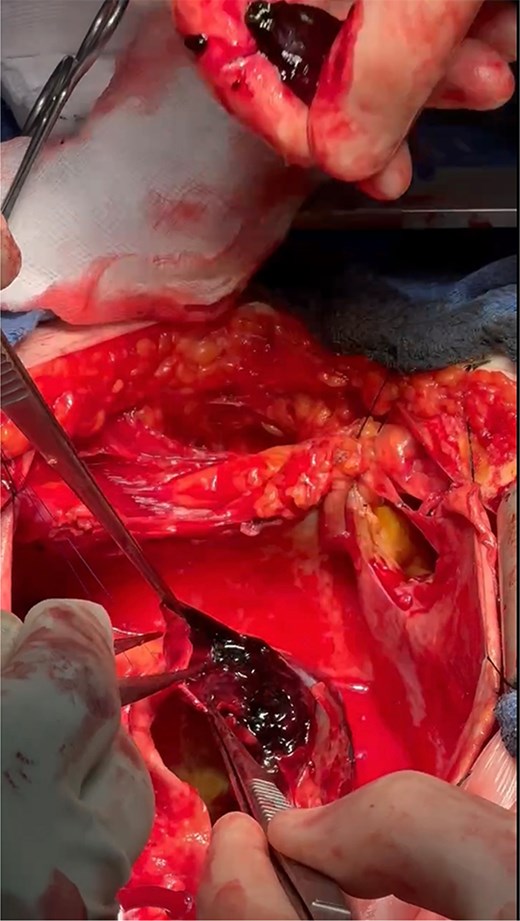

The operation was performed via median sternotomy, with the aneurysm immediately visible post sternotomy (Fig. 5). The pericardium was carefully opened without complication, and due to the right atrium being inaccessible, cardio-pulmonary bypass was established using central ascending aortic cannulation and femoral venous cannulation, with antegrade cardioplegia (Fig. 5). The giant CAA was then opened directly where it was uncovered that the aneurysm wall had also dissected, and was paper thin (Fig. 6). The thrombus was evacuated, perforating branches were identified and oversewn, of which there were two. Following this, an endoscopically harvested saphenous vein graft was used to directly, end-to-end anastomose the proximal and distal necks of the aneurysm, bypassing the sac entirely (Fig. 7). The patient was successfully weaned from Cardiopulmonary Bypass and the procedure concluded without complication.